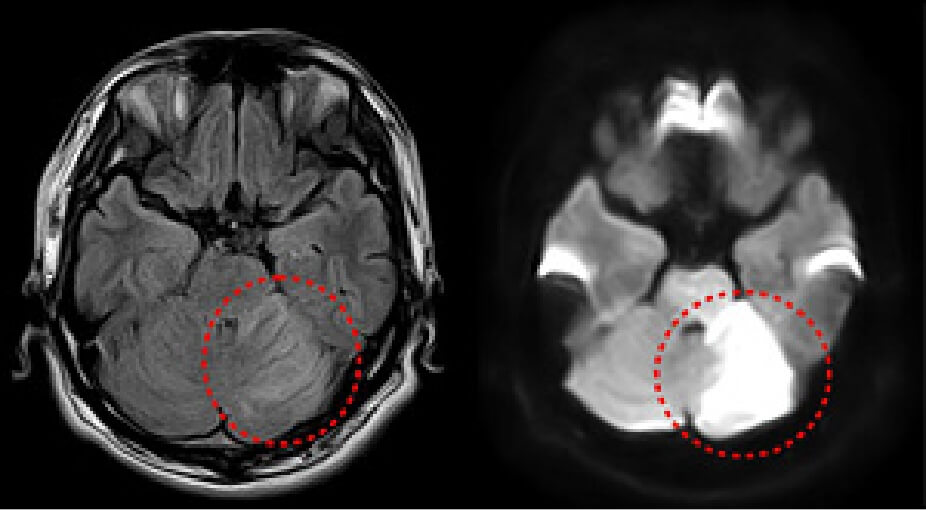

左図と同部位に梗塞のある症例